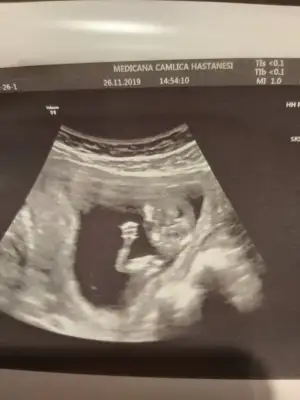

Ama o nub çıkıntısı değil ayak sankiBunu ben bile anladım bu erkek![]()

erkek gibi başka usg var kaç haftalık

Öğrendiniz mi neymiş ben genelde kıza benzetiyorum nedenseBenim de kız demiştiniz![]()